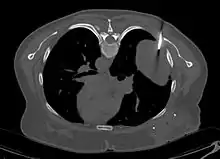

- Tumeur fibreuse solitaire du rein

Aspect tomodensitométrique. La tumeur est repérée par les flèches[46].

En tomodensitométrie[20],[31], quelle que soit la localisation, une tumeur fibreuse solitaire apparaît comme une masse tissulaire ovoïde ou lobulée, bien délimitée, refoulant les structures voisines sans les envahir. Elle se rehausse fortement après injection de produit de contraste. Les tumeurs de petite taille sont homogènes, mais les plus volumineuses présentent des plages hétérogènes de nécrose et d'hémorragie intra-tumorale. Il n'y a pas habituellement de calcifications et, lorsqu'elles sont présentes, elles sont de petite taille[31]. Les tumeurs malignes peuvent se présenter accompagnées de nodules pulmonaires métastatiques, et tendent à être plus volumineuses et plus hétérogènes[42].